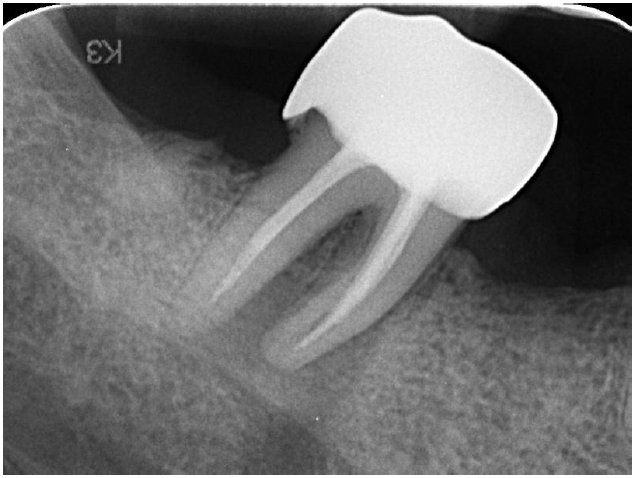

A 52-year-old male patient presented in 2021 with acute, severe pain localized to tooth 47 (mandibular right second molar). Clinical and radiographic examination revealed a large periapical lesion at tooth 47, despite the presence of a previous root canal treatment, and a compromised tooth 16 with extensive structural loss, subgingival decay, and perforation.

Large periapical lesion on tooth 47

Radiograph with initial treatment